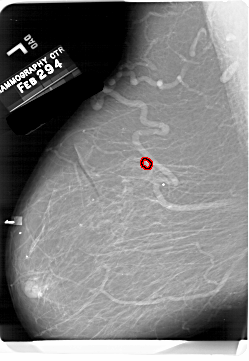

A_1701_1.RIGHT_CC

RIGHT_CC LINES 6541 PIXELS_PER_LINE 4681 BITS_PER_PIXEL 12 RESOLUTION 43.5 NON_OVERLAY

FILE: A_1701_1.LEFT_CC.OVERLAY

TOTAL_ABNORMALITIES 1

ABNORMALITY 1

LESION_TYPE MASS SHAPE IRREGULAR MARGINS SPICULATED

ASSESSMENT 5

SUBTLETY 3

PATHOLOGY MALIGNANT

TOTAL_OUTLINES 2

BOUNDARY

CORE